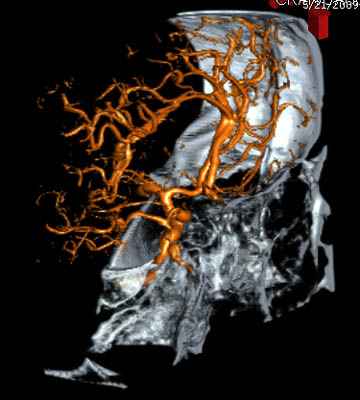

По протоколу сделаны все необходимые исследования: рентген, ангиограмма с 3Д реконструкцией, где обнаружили что все жизненно важные сосуды не задеты, даже некоторые "сидят" изгибаясь на ноже.